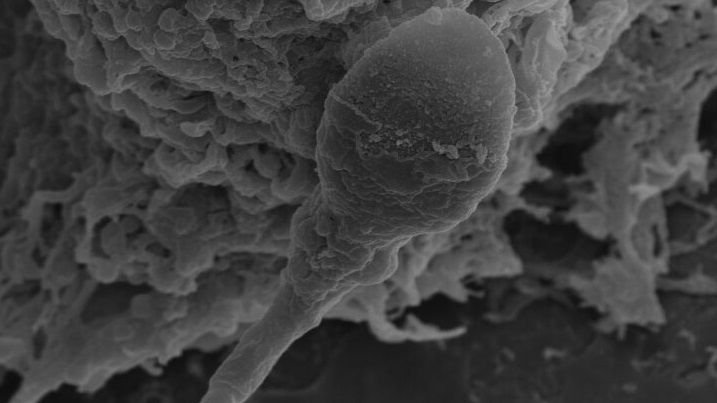

Can humans have babies in space? It may be harder than expected

When you buy through links on our articles, Future and its syndication partners may earn a commission. Humankind is bound to become a space-faring species, expanding beyond the bounds of Mother Earth, just as it, millions of years ago, spread out of its cradle in Africa. At least that's what space exploration leaders such as the world's richest man Elon Musk would like you to believe. However, there may be biological hurdles that could forever confine this vision to the realm of science fiction and human civilization to our Earthly soil. A new study found that sperm cells of mammalian species including humans, mice and pigs struggle to find their way through a female reproductive tract in microgravity to reach and fertilize an egg. Even when the sperm makes it to its destination, the study found that embryos formed in these conditions develop poorly compared to those evolving in normal gravity. The study, from researchers at the University of Adelaide in Australia, is just the latest addition to a growing pile of evidence that suggests mammalian reproduction in space might be quite complicated, if not impossible. There have been some previous studies with headlines stating mouse babies were born from stem cells subjected to months-long spaceflight, but most earlier research, conducted either in space or in microgravity simulators on Earth, has revealed a plethora of negative effects the space environment has on reproductive cells and embryos. "When you think about the future of space exploration and space settlements, it's happening. It's happening now," Nicole McPherson, a reproductive biologist at the University of Adelaide, Australia, and lead author of the paper, told Space.com. "I think people forget that for us to maintain these settlements without having to continually colonize them from Earth, we need to be able to reproduce in space." McPherson, whose previous work covered the effects of obesity and diet on the success of conception, got intrigued by the question of the possibility of in-space reproduction after watching a documentary hosted by British physicist Brian Cox. A discussion with her partner then spawned an idea for a unique research experiment. A chance encounter with the founder of space medicine company Firefly Biotech a week later allowed her to acquire a 3D clinostat for her lab. This device is a high-tech centrifuge that simulates microgravity by spinning vials with samples around two axes, effectively confusing the cells inside as to their position in space. In her experiment, McPherson and colleagues created a set-up holding human, mice and pig sperm cells in one part of the compartment and egg cells in the other, divided by a thin channel simulating the female reproductive tract. The researchers observed that 30% fewer sperms were able to make it to the egg compared to those in normal gravity. Scientists know sperm relies on a complex set of signals to find its way to an egg. Part of that navigation is driven by chemical cues, such as concentrations of the female hormone progesterone, but gravity seems to play a significant role too, McPherson said. "We know that sperm responds to chemical cues, but we also know that they like to swim near surfaces," she said. "Obviously, to know where surfaces are, you need to understand your position in time and for that you need gravity." The struggle of sperm to make it to the egg was only one part of the findings. When sperms managed to reach the eggs, the ensuing early-stage embryos, called blastocysts, initially appeared stronger than their counterparts conceived in gravity. However, when microgravity exposure continued, the superior quality of microgravity-conceived blastocysts deteriorated and the embryos started to lag behind their normal counterparts. McPherson thinks the initial quality gain observed in embryos formed after only four hours of microgravity exposure was due to the natural selection process that had occurred, allowing only the fittest sperms to reach the eggs. The subsequent deterioration in embryos that had been in microgravity for up to 24 hours was likely due to negative effects the absence of gravity has on the processes taking place in the quickly dividing embryonic cells. "There are so many changes that happen in those first 24 hours of embryo development," McPherson said. "You have the maternal and the paternal DNA coming together. You have lots of epigenetic remodeling that goes on to drive early foetal development. And that being exposed to zero gravity is actually really detrimental." McPherson said the researchers would, in the future, want to conduct similar experiments in reduced gravity, such as that of the moon or Mars, to see whether partial gravity might mitigate the problem. She thinks the findings have implications not just for the visions of space settlements, but also for commercial space tourism and babies potentially conceived on lunar and orbital honeymoons. The natural selection leading to the formation of stronger embryos after short microgravity exposures, on the other hand, could lead to advances in human IVF technologies that help treat infertility on Earth. In the future, the researchers would like to expose the embryos to longer microgravity spells to gain deeper insights into the processes taking place in space-like conditions. The study was published in the journal Communications Biology on Thursday (March 26).